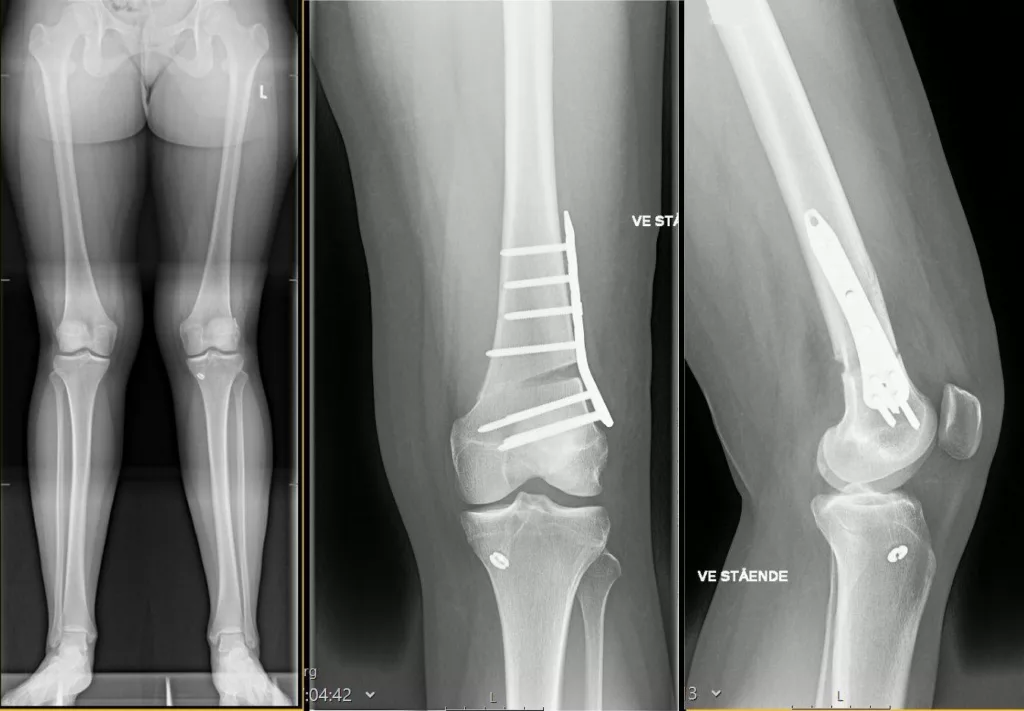

L’ostéotomie fémorale de varisation (OFV) consiste à couper une partie du fémur pour corriger son défaut d’axe. En cas de jambes désaxées en varus (jambes arquées) ou en valgus (jambes en X), les contraintes sont moins bien réparties dans le genou, source de douleurs et d’usure du cartilage (arthrose).

En réalignant correctement la jambe on répartit correctement les contraintes au centre du genou ce qui soulage les douleurs, retarde l’apparition de l’arthrose et augmente la durée de vie l’articulation. Cette chirurgie est particulièrement adaptée avant l’âge de 60 ans en cas d’arthrose modérée. Après 65 ans, on discute plutôt une pose de prothèse unicompartimentale (PUC) du genou.

Cette intervention nécessite une correction très précise, pour cela une planification 3D de votre genou est réalisée à l’aide d’un scanner et des guides de coupe sur mesure sont produits pour s’adapter parfaitement à votre genou et obtenir la correction nécessaire.

Une incision d’environ 15cm est réalisée à la partie basse du fémur pour positionner les guides et réaliser la coupe sur mesure. L’ostéotomie est ensuite ouverte pour réaxer la jambe selon la planification. Elle est fixée par une plaque métallique et des vis. L’espace créé par l’ouverture est greffé par un substitut osseux pour accélérer la consolidation de l’os.